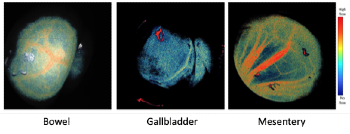

Laser Speckle Contrast Imaging (LSCI) is a non-invasive imaging technique used to visualize vascular or tissue perfusion by creating speckle patterns on the target tissue. Compared to fluorescence imaging, which requires the injection of contrast agents, LSCI permits uninterrupted visualization of blood flow and tissues without the use of surgical dyes; however, current LSCI techniques require the integration of the laser light source, fiber light guide coupling and specular reflections from tissue surfaces, and the creation of multiple incisions for ideal illumination by different lights source to counter adverse effects of shadow and angle-dependent, uneven lights.

- Single port used

- No contrast dye injection required

- Continuous and real‐time visualization

- Easily adaptable with fluorescence laparoscopy